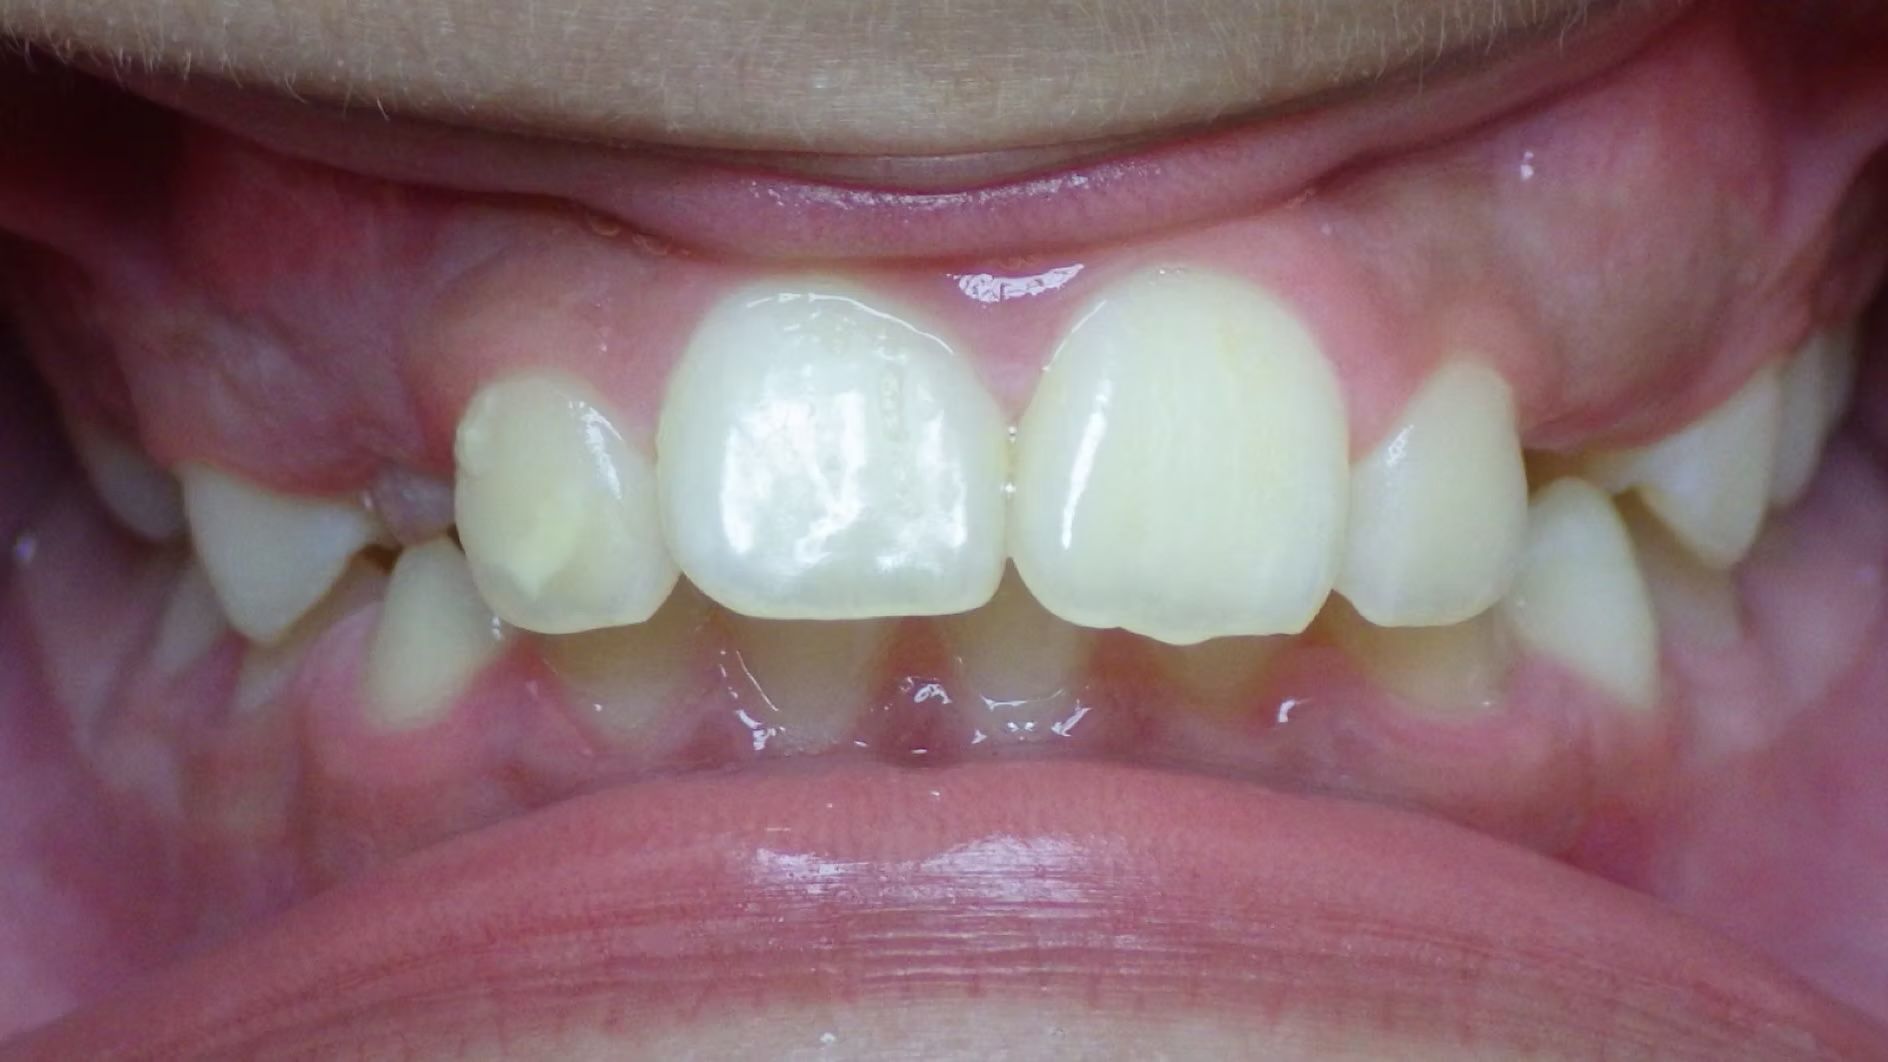

IAN

Ian came to the office because his lower teeth were crowded and he had an anterior cross bite. With traditional braces we resolved the crowding and aligned the teeth without causing flaring of the incisors and giving him a handsome smile. The treatment lasted 18 months and the final photos are at a 2 year follow up when we made him a new clear retainer.